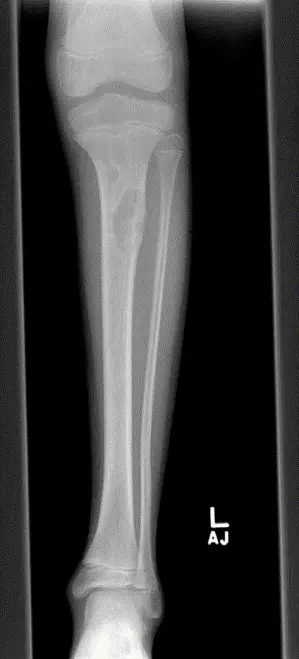

- الأشعة السينية (X-ray): هي الفحص التشخيصي الأول والأكثر أهمية. يظهر الورم الليفي غير المتعظم عادةً كآفة بيضاوية أو متعددة الفصوص (فقاعية الشكل) شفافة للأشعة (منطقة داكنة) في قشرة العظم، مع حافة صلبة (بيضاء) مميزة (Sclerotic Rim). يعتمد الأستاذ الدكتور هطيف بشكل كبير على خبرته في قراءة هذه الصور لتأكيد التشخيص واستبعاد الآفات الأخرى.

1. مرحلة التحلل (Lytic Phase): تظهر الآفة كمنطقة داكنة (شفافة للأشعة) في العظم.

2. مرحلة التصلب (Sclerotic Phase): تبدأ الآفة في التصلب من الحواف نحو المركز، وتصبح أكثر كثافة.

3. مرحلة الشفاء (Healing Phase): يتم استبدال النسيج الليفي تدريجيًا بعظم طبيعي، وتختفي الآفة تمامًا مع مرور الوقت، تاركة وراءها منطقة عظمية طبيعية.